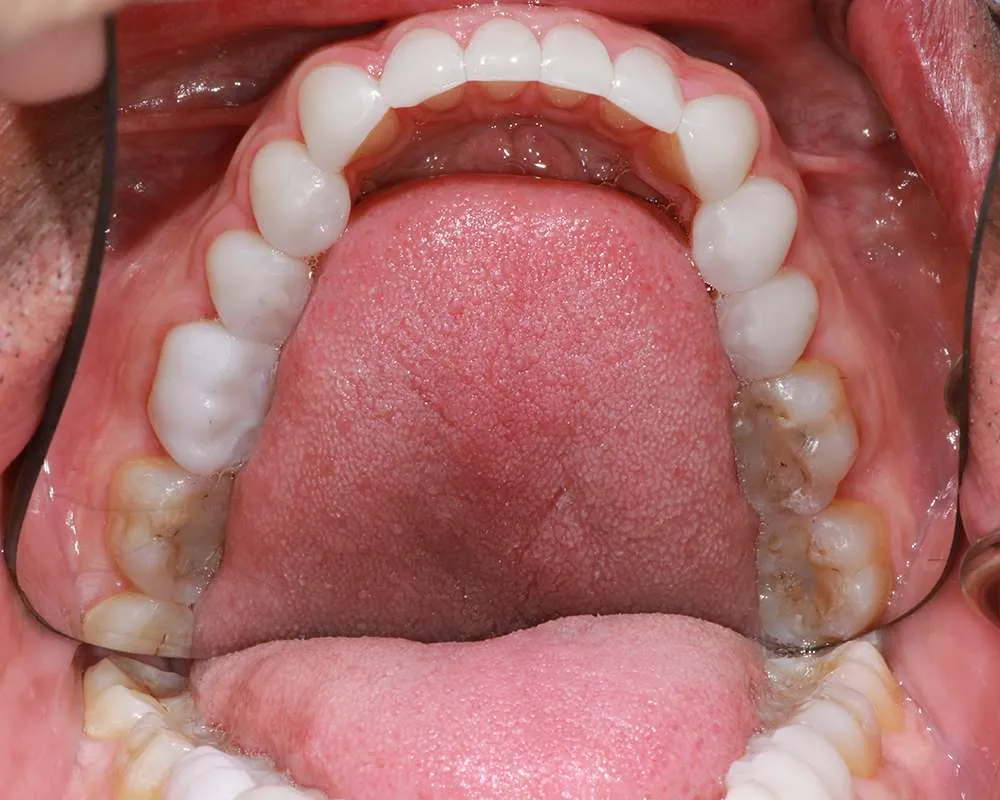

Real Stories, Real Results: Case Studies Showcasing How Our Personalized Approach Transforms Smiles and Lives

Witness the Remarkable Changes We Can Achieve

Ultra-thin veneers are crafted from high-quality materials that closely resemble the look and feel of natural teeth. The translucency and texture of these veneers mimic the appearance of real enamel, ensuring that your smile looks natural and aesthetically pleasing. Each veneer is custom-made to match the color, shape, and size of your existing teeth, blending seamlessly with your natural smile. This attention to detail ensures that your veneers are virtually indistinguishable from your natural teeth, providing you with a flawless, beautiful smile.

Achieving a transformed smile with ultra-thin veneers is a relatively quick process that can be completed in just a few visits to our office. After the initial consultation and planning, the preparation and placement of the veneers are straightforward and efficient. Unlike more invasive procedures that require multiple stages and extended recovery times, ultra-thin veneers offer a faster route to a beautiful smile. You can achieve noticeable improvements in the appearance of your teeth in a short period, allowing you to enjoy the benefits of a stunning smile with minimal disruption to your daily life.